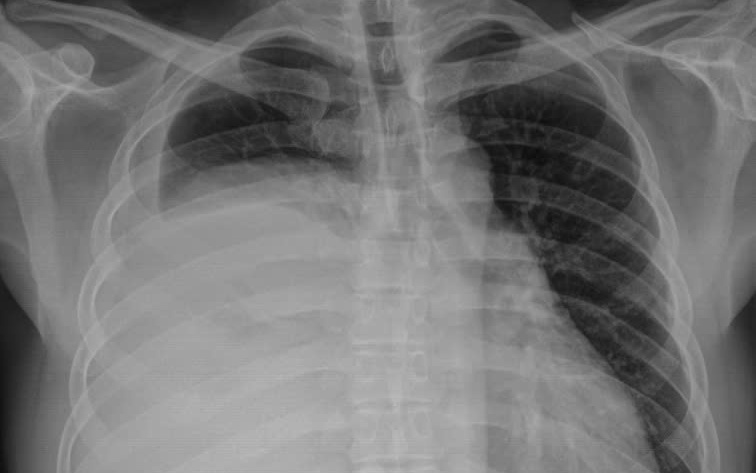

Người đàn ông 42 tuổi mang khối u nặng 3,6kg trong lồng ngực mà không biết

GĐXH - Khối u trung thất khổng lồ, có kích thước lên tới 30x20 cm, nặng 3,6 kg. Đây là một trong những khối u lớn hiếm gặp trong y văn, đe dọa nghiêm trọng đến chức năng hô hấp của người bệnh.